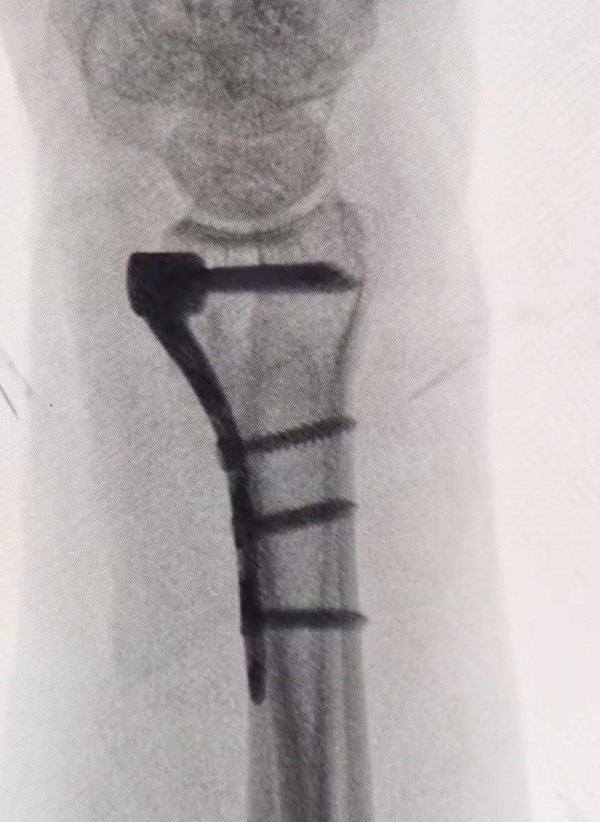

(2)多数骨折通过改良Henry入路、行掌侧钢板固定可以获得满意疗效。

但是对于:①合并关节面塌陷的桡骨茎突剪切骨折、复杂四部分粉碎性骨折,其背侧月骨面部分骨块不能通过掌侧入路复位;②合并腕骨间韧带断裂的复杂性骨折;③伤后3周或更长时间发生的背侧移位骨折,则需要考虑背侧入路、或掌背侧联合入路行钢板固定及辅以外固定架辅助治疗。